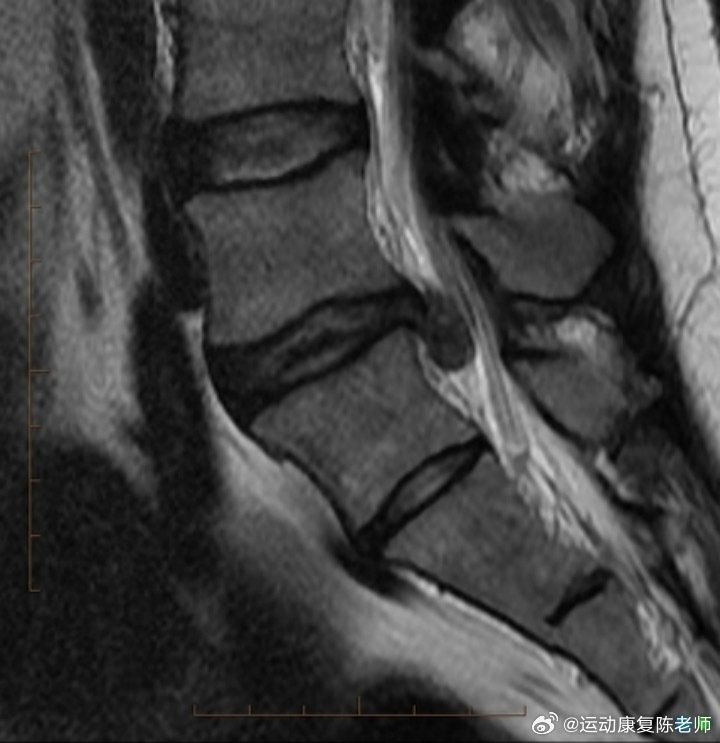

👉【腰椎间盘脱出】图3.6这是腰椎间盘病变最为严重的阶段。纤维环完全破裂,髓核从破裂处挤出,游离到椎管,对神经根的压迫更为严重。

不仅会感觉到剧痛,还可能出现马尾神经症状,如大小便障碍(便秘或大小便失禁)、会阴部异常等。此外,压迫神经根还可能导致一侧腿疼、腿麻等症状。